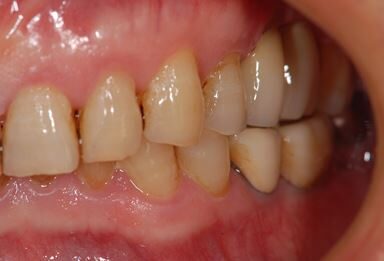

インプラントの症例写真 IMPLANT

抜歯即日スピードインプラント治療

| 治療内容 | インプラント2本(抜歯即日スピードインプラント) | ||||||||||||||||||||||||||||||||

| 治療期間 | 10ヶ月 |